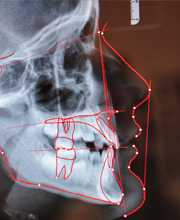

Geometrische Wachstumsanalyse der Seitröntgenaufnahme

Mit Hilfe der sog. Fernröntgenanalyse lässt sich nicht nur der Aufbau des Gesichtsschädels, sondern durch Überlagerungen mit älteren Aufnahmen auch das individuelle Wachstumsmuster erkennen. Dies ist von unschätzbarem Wert für die Steuerung des Wachstums während der Behandlung.